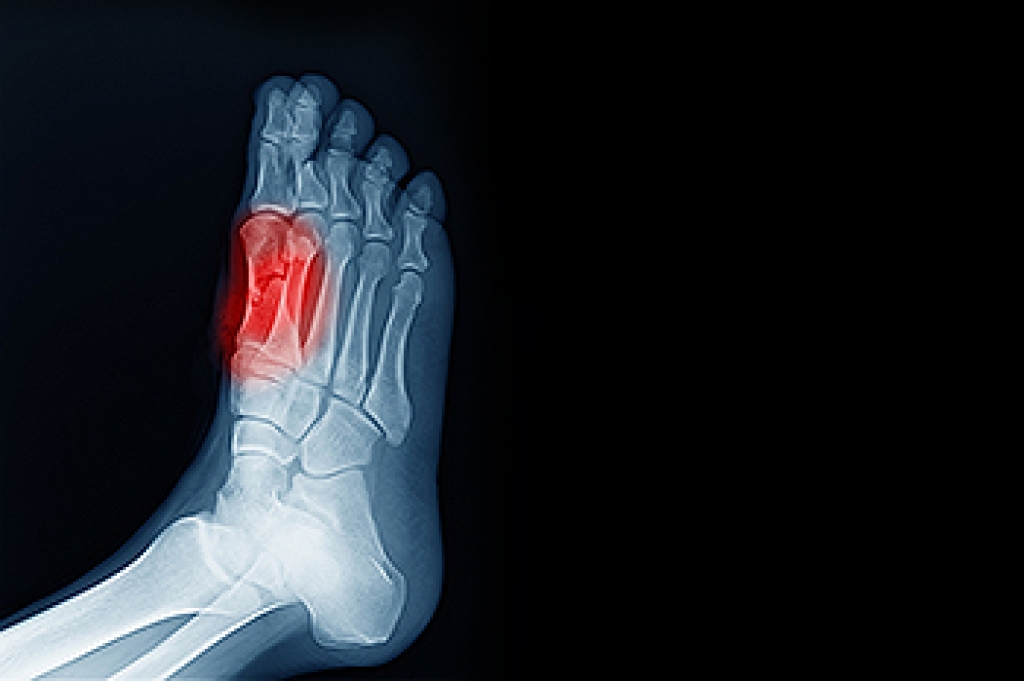

Possible Causes of Sesamoiditis

Sesamoiditis, a condition that impacts the tiny sesamoid bones beneath the big toe joint, unveils itself as inflammation in this delicate area. These small, pea-shaped bones play a vital role in weight-bearing and facilitating smooth movement of the foot. Sesamoiditis typically arises from overuse or repetitive stress on the forefoot, particularly common among athletes engaging in activities that involve frequent pushing off the toes. Ballet dancers, runners, and individuals participating in high-impact sports are often susceptible. The condition may also be triggered by structural abnormalities in foot anatomy, such as having a high arch, or from wearing improper footwear that fails to adequately cushion and support the ball of the foot. Recognizing the causes of sesamoiditis helps individuals take preventive measures, including wearing proper footwear, and modifying activities to protect these small yet significant bones in the intricate structure of the foot. Sesamoiditis is a condition that is treated by a podiatrist. If you have developed this condition, it is strongly urged that you schedule an appointment with this foot doctor who can offer you effective treatment options.

Sesamoiditis is an unpleasant foot condition characterized by pain in the balls of the feet. If you think you’re struggling with sesamoiditis, contact Edward Orman, DPM of Honeygo Podiatry. Our doctor will treat your condition thoroughly and effectively.

Sesamoiditis

Sesamoiditis is a condition of the foot that affects the ball of the foot. It is more common in younger people than it is in older people. It can also occur with people who have begun a new exercise program, since their bodies are adjusting to the new physical regimen. Pain may also be caused by the inflammation of tendons surrounding the bones. It is important to seek treatment in its early stages because if you ignore the pain, this condition can lead to more serious problems such as severe irritation and bone fractures.

Causes of Sesamoiditis

- Sudden increase in activity

- Increase in physically strenuous movement without a proper warm up or build up

- Foot structure: those who have smaller, bonier feet or those with a high arch may be more susceptible

Treatment for sesamoiditis is non-invasive and simple. Doctors may recommend a strict rest period where the patient forgoes most physical activity. This will help give the patient time to heal their feet through limited activity. For serious cases, it is best to speak with your doctor to determine a treatment option that will help your specific needs.

If you have any questions, please feel free to contact our offices located in Perry Hall, and Fallston, MD . We offer the newest diagnostic and treatment technologies for all your foot care needs.